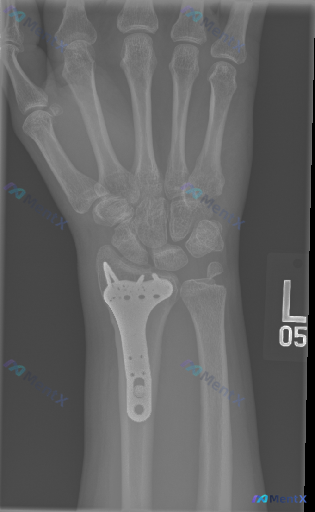

整理到一份左腕关节正位X光片的术后复查影像资料,给大家分享一下关键表现,一起讨论看看: - 左侧桡骨远端有金属钢板及多枚螺钉固定,钢板位置主要在掌侧/掌桡侧 - 骨折断端对位良好,皮质连续性尚可,未见明显透亮骨折线 - 腕骨(舟骨、月骨、三角骨等)形态、密度未见明显异常,无明显骨折脱位 - 桡腕关节...